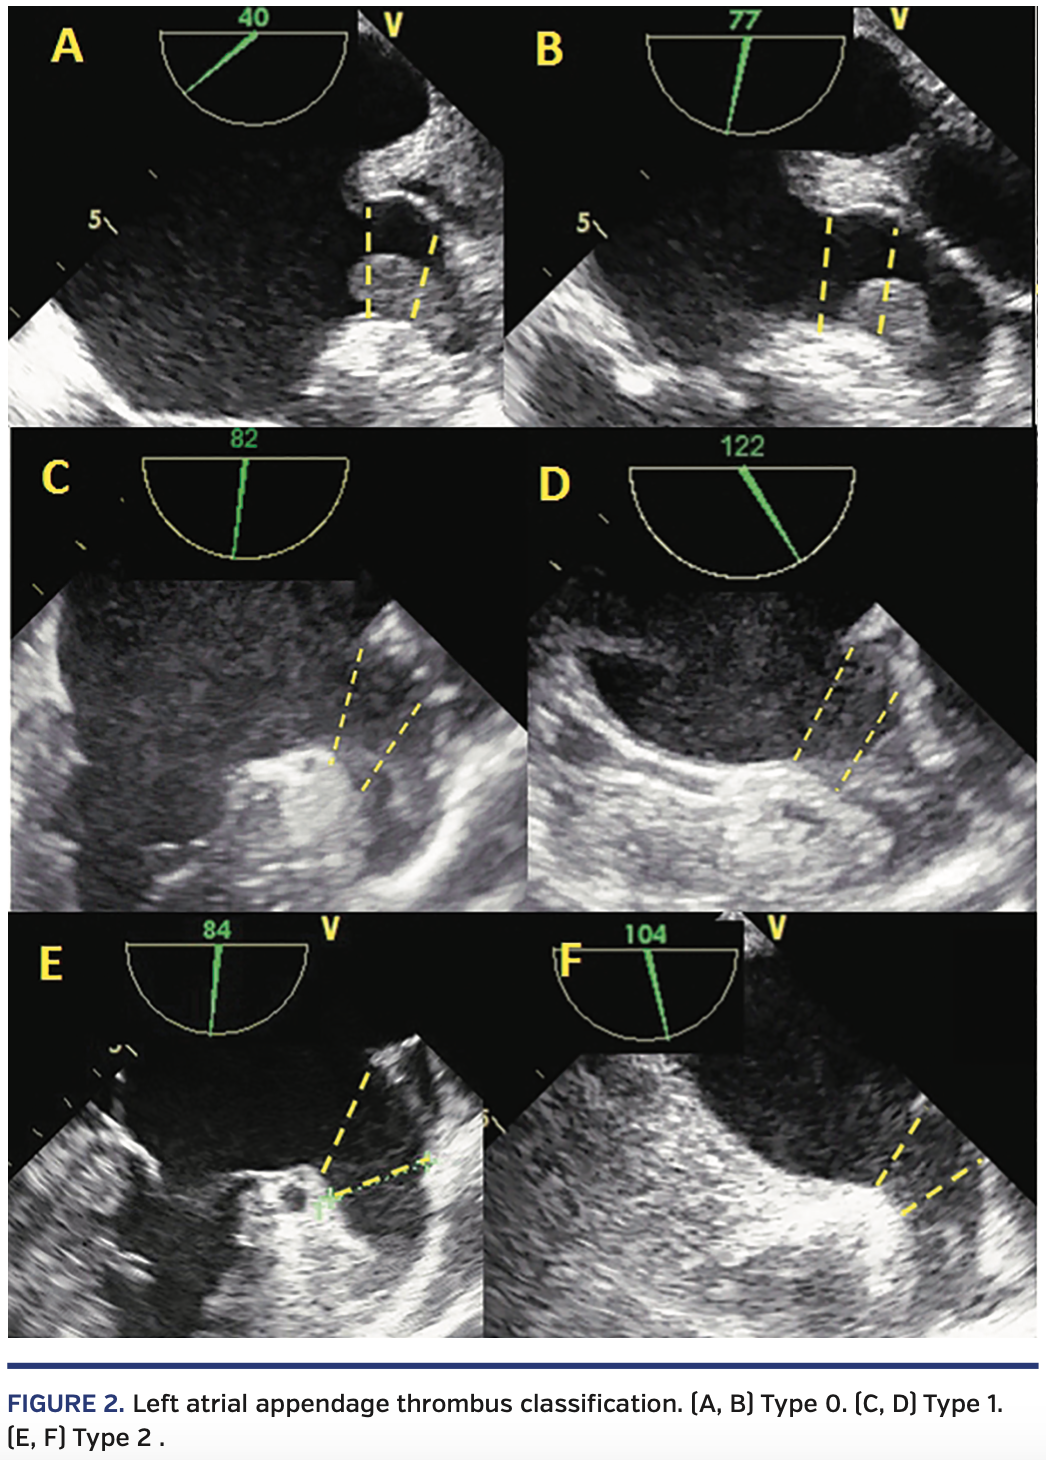

LAA thrombi were classified according to the location. The LAA is divided into three different sections (Figure 1). The first section is outside of the LAA. The second section is a 10 mm distance from the LAA ostium (landing zone). The third section is the base of the LAA. If any part of the thrombus is in the first section, it is classified as type 0 (overflowing thrombus). If any part of the thrombus is in the second section but not in the first section, it is classified as type 1 (proximal to mid thrombus). If thrombus is located in the third section and has no part in the second section, it is classified as type 2 (mid to distal thrombus) (Figure 2). Type 0 thrombi were excluded and LAA occlusion was not performed in these patients.